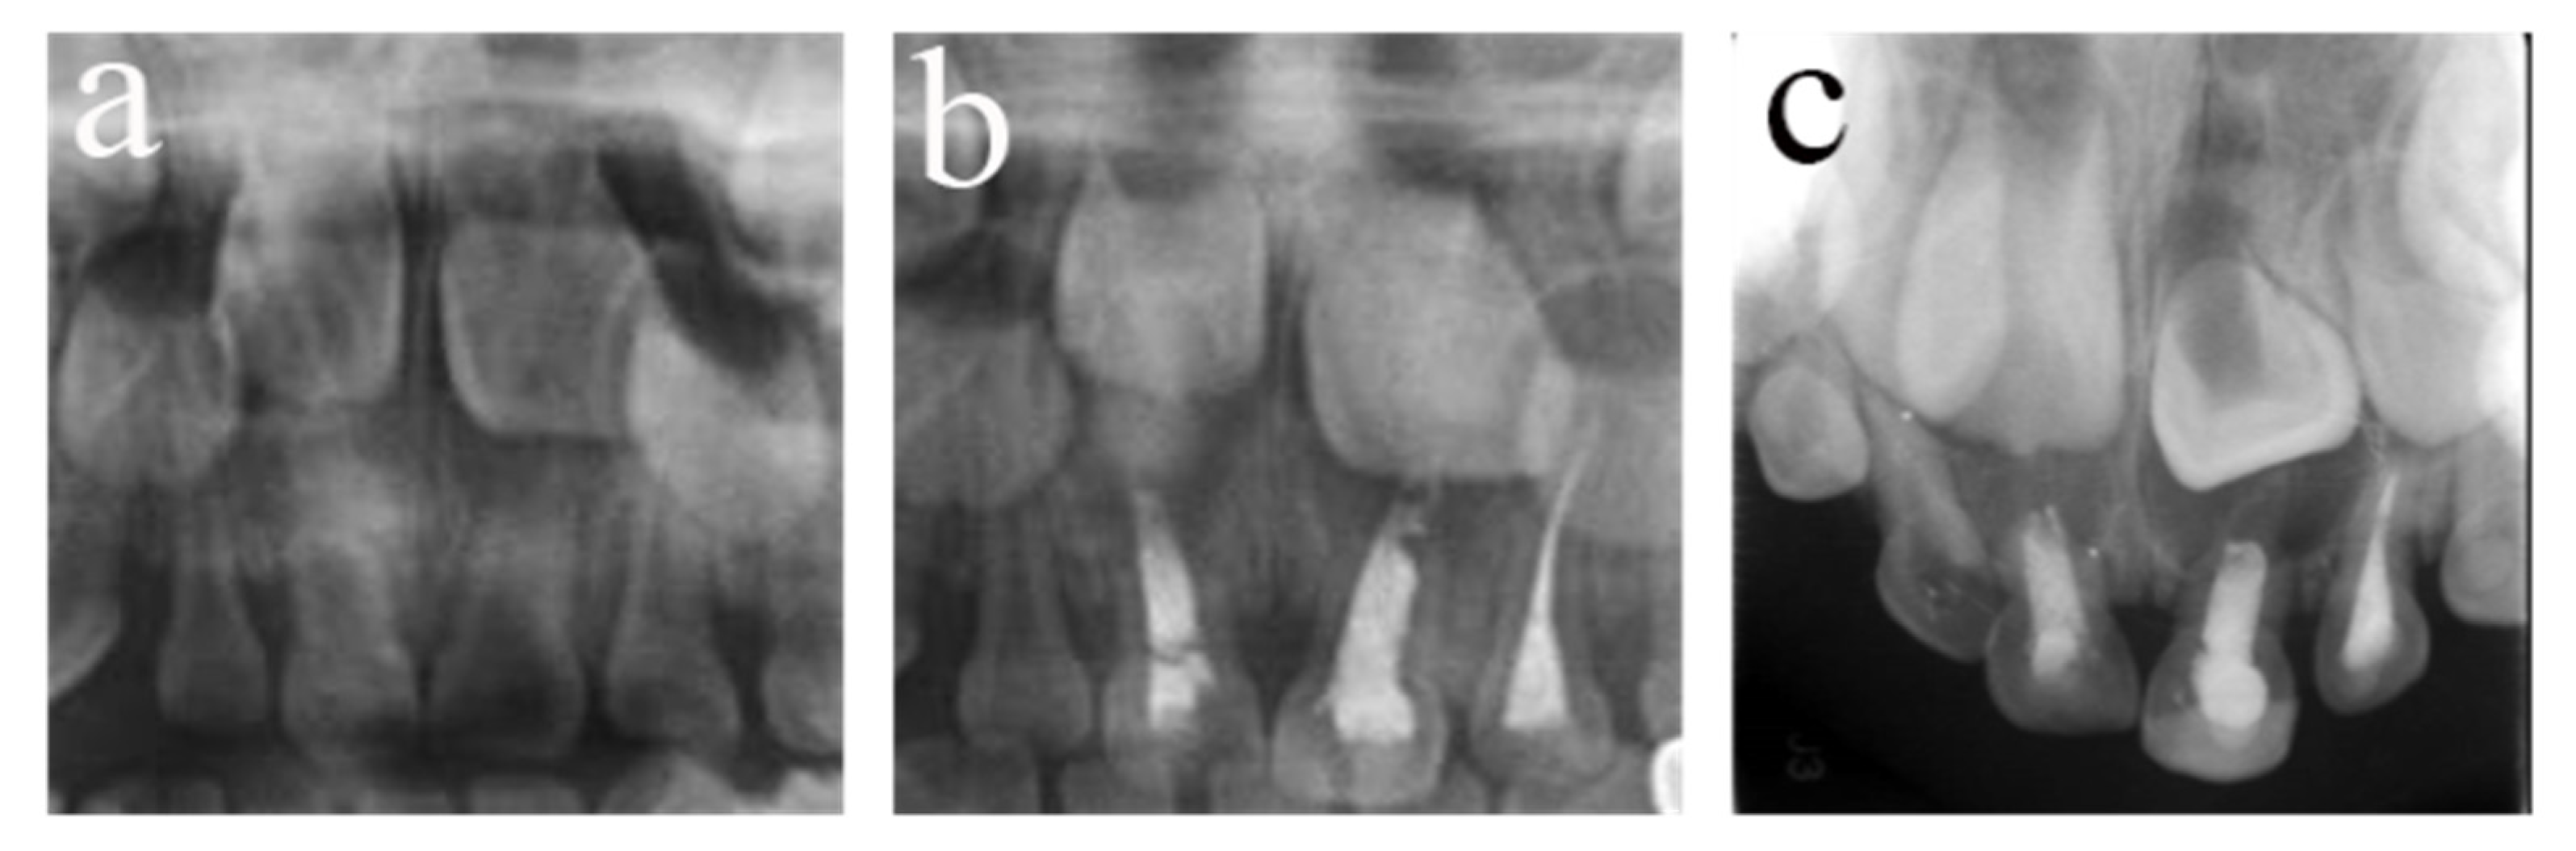

Figure 5.

#54 received pulpectomies under DGA with a 34-month follow-up period (65-month-old male child). (a) The preoperative radiograph revealed periapical radiolucency surrounding #54. (b) Radiograph taken one week postoperatively showing overfilling in the buccal root canals. (c) Twenty-six months after the operation, the root was completely absorbed, and the eruption direction of #14 was altered. Pulpectomies in #54 failed.

Figure 6.

#64 received pulpectomies under DGA with a 32-month follow-up period (63-month-old male child). (a) The preoperative radiograph revealed nothing abnormal in the periapical area. (b) Radiograph taken one week postoperatively showing optimal filling. (c) Thirty-two months after the operation, #64 was lost early, and #24 erupted prematurely. Pulpectomies in #64 failed.